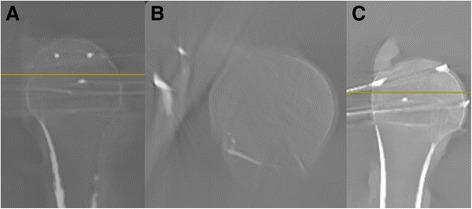

The purpose of this study was to investigate the accuracy of perforation detection with multiplanar reconstructions using a mobile 3D image intensifier.

METHODS

In 12 paired human humeri, K-wires perforating the subchondral bone and placed just below the cartilage level were directed toward five specific regions in the humeral head. Image acquisition was initiated by a fluoroscopy scan. Within a range of 90°, 45° external rotation (ER) and 45° internal rotation (IR). The number and percentage of detected perforating screws were grouped and analyzed. Furthermore, the fluoroscopic images were converted into multiplanar CT-like reconstructions. Each K-wire perforation was characterized as "detected" or "not detected".

In the series of fluoroscopy images in the standard neutral position at 30° internal rotation, and 30° external rotation, the perforations of all K-wires (n = 56) were detected. Twenty-nine (51.8%) of them were detected in one AP view, 22 (39.3%) in two AP views, and five (8.9%) in three AP views. All K-wire perforations (100%, n = 56) were detected in multiplanar reconstructions.

CONCLUSION

In order to reveal all of the intraoperative and postoperative screw perforations in a "five screw configuration", conventional AP images should be established in both the neutral positions (0°), at 30° internal rotation and 30° external rotation. Alternatively, the intraoperative 3D scan with multiplanar reconstructions enables a 100% rate of detection of the screw perforations.